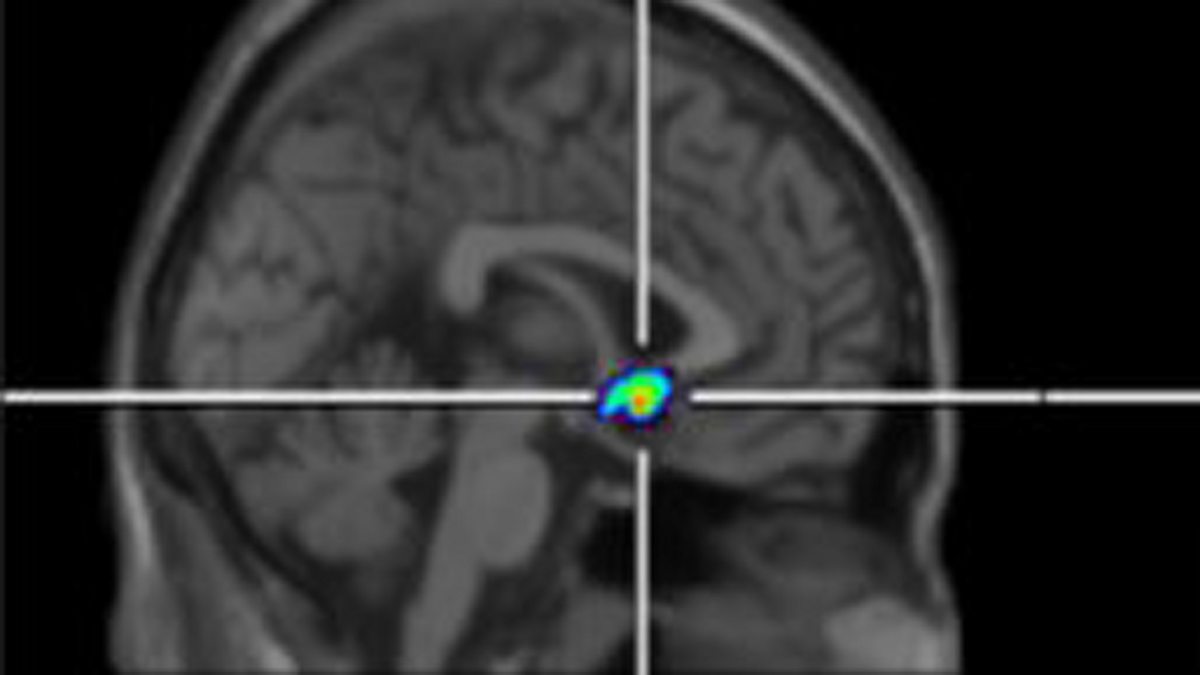

They have known for a while that we have receptors in our brain, like tiny docking stations, that link up with natural painkilling opiates like endorphins to reduce pain. But now for the first time, researchers have shown that the numbers of these opiate receptors seem to increase in response to pain, naturally increasing our pain thresholds and helping people with chronic pain cope better. Anthony Jones is professor of neuro-rheumatology at the University of Manchester, and his research has just been published in the journal Pain.

Picture: Patients with chronic pain have differences in opioid receptors in a region of the brain that processes pain and motivation.

Credit: Human Pain Research Group, University of Manchester